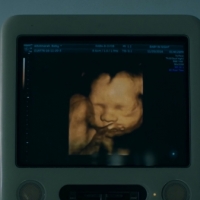

MVは様々なアーティストを手掛ける新進気鋭の作家、小島央大が担当し「世界の解像度」をキーワードに人が世界を見る視点が大きく変わるような起点として「死」と「生」に直面する場面を軸に、楽曲の多様なテーマ性を解釈して制作された。

今の自分自身の感情状態によって楽曲の世界観の中でどのように物語の二人が映るのかも同時に感じられる作品となっている。